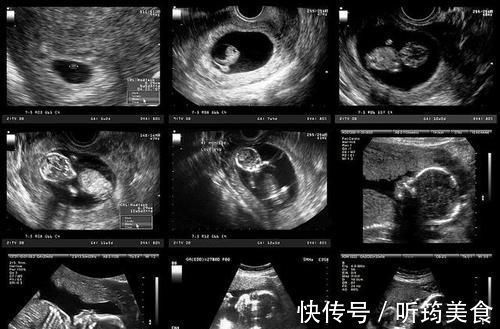

B超的工作原理是声波与光波技术结合而成,通过特殊的算法,将这些检测手段反馈的数据进行分析,最后形成图形供给医生诊断。

然而,由于技术上的限制,该算法尚未完善,因此,最终的成像结果也达不到清晰可见的程度,医生在诊断时,大部分判断依靠专业知识,而剩下的只能靠经验以及感觉。